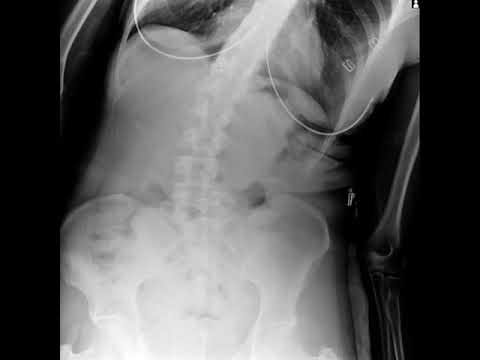

One of the cool things they offer is **advanced L Spine X-Ray technology**. Sounds fancy, huh? Well, it really is! This special type of X-ray helps doctors take a closer look at your lower back—where the lumbar spine hangs out. Why does that matter? Because it can help identify issues like fractures or disc problems that might be causing some discomfort.

They’ve got the skills to tackle all sorts of spinal issues. You know, herniated discs, scoliosis or just plain old back pain that won’t quit. What’s cool is that they utilize advanced technology for diagnosis and treatment. One of the latest tools on the scene is L Spine X-Ray technology.

L Spine X-Ray offers super detailed images of your spine without any fuss. It helps in spotting problems quickly and accurately. Imagine you’re going in for a check-up and getting clear pictures of what’s happening inside—kinda like an X-ray but specifically tailored for your spine!

One cool thing they have? Advanced L Spine X-Ray technology. Seriously, it’s high-tech stuff! This allows doctors to see your spine in detail without invasive procedures. They can spot issues early on and figure out the best way to help you out—like a superhero with x-ray vision!

Now, let’s talk about one cool thing: their use of L Spine X-Ray technology. It’s like getting a super-clear snapshot of your spine. Imagine trying to find a specific friend in a crowded concert; if you have a zoomed-in photo, it’s way easier! This tech lets them see exactly what’s going on and helps them figure out the best course of action for you.

- Advanced Imaging: Their L Spine X-Ray gives detailed views for accurate assessments.

Now here’s where it gets interesting: advanced L spine X-ray technology can really make a difference. They’re not just taking old-school snapshots anymore! The images are clearer and more detailed, which helps doctors see what’s going on with your health—like whether there’s any misalignment or damage. Imagine being able to catch those issues early before they become something serious? That’s kinda impressive if you ask me.